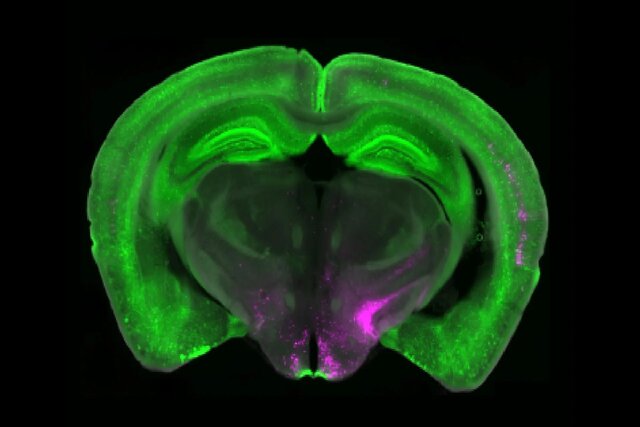

بتلی به همراه پژوهشگران «دانشگاه پیتسبرگ»(University of Pittsburgh) و «مؤسسه پژوهشی اسکریپس»(Scripps Research Institute)، قطعه مهمی را از پازل درد مزمن کشف کردهاند. تحقیقات آنها به گروه خاصی از سلولهای بنیادین مغز به نام «نورونهای بیانکننده گیرنده»(Y1R) اشاره دارد که در «هسته پارابراکیال»(Parabrachial nucleus) مغز قرار گرفتهاند. این نورونها در حالتهای درد مداوم فعال میشوند، اما سیگنالهای مربوط به گرسنگی، ترس و تشنگی را نیز پردازش میکنند. این نشان میدهد که مغز میتواند واکنش به درد را در زمان نیازهای فوریتر تنظیم کند.

گروه بتلی با همکاری پژوهشگران «آزمایشگاه تیلور»(Taylor lab) در دانشگاه پیتسبرگ، از تصویربرداری کلسیم برای به تصویر کشیدن در لحظه فعالیت نورونها در مدلهای حیوانی درد کوتاهمدت و بلندمدت استفاده کردند. آنها دریافتند که نورونهای Y1R صرفاً به حملات سریع درد واکنش نشان نمیدهند، بلکه در طول درد بلندمدت به طور پیوسته فعال میشوند. این پدیده به عنوان «فعالیت تونیک»(Tonic activity) شناخته میشود.

این اطلاعات، الهامبخش تحقیقات بیشتر شدند. «نیتسان گلدشتاین»(Nitsan Goldstein)، دانشجوی سابق کارشناسی ارشد دانشگاه پنسیلوانیا دریافت که سایر حالتهای حیاتی بقا مانند تشنگی و ترس نیز میتوانند درد بلندمدت را سرکوب کنند. این گروه پژوهشی با همکاری «آزمایشگاه کندی»(Kennedy lab) در مؤسسه پژوهشی اسکریپس نشان دادند که وقتی بقای فوری در اولویت قرار میگیرد، هسته پارابراکیال مغز میتواند ورودیهای حسی را نسبت به درد آرام فیلتر کند.

پژوهشگران در این پروژه، هویت مولکولی و آناتومیکی نورونهای Y1R را در هسته پارابراکیال مشخص کردند. آنها دریافتند که نورونهای Y1R، دو جمعیت آناتومیکی یا مولکولی منظم را تشکیل نمیدهند. در عوض، این نورونها در بسیاری از انواع سلولهای دیگر پراکنده شدهاند.